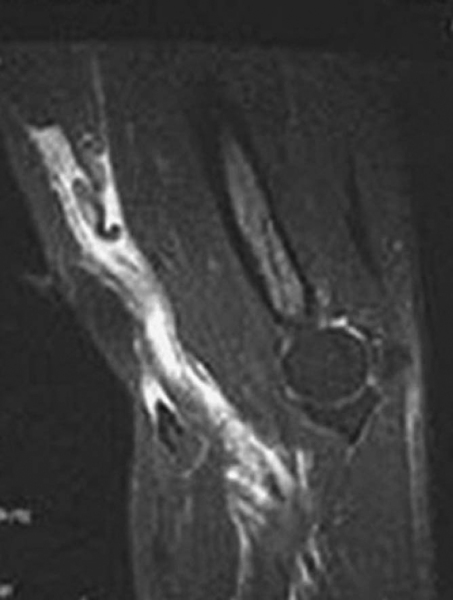

If the physical examination is conclusive, further imaging is not required; but magnetic resonance imaging can help confirm the diagnosis if the physical examination findings are unclear. Magnetic resonance imaging may also help identify the extent and location of injury, which may aid in surgical planning. For example, rupture at the myotendinous junction, although rare, can present difficulty when a standard surgical technique is attempted. In complete ruptures, findings include absence of the tendon distally, fluid-filled tendon sheath, muscle edema, and atrophy (

Fig. 41-2

).[8] For partial rupture, magnetic resonance imaging can reveal high signal and fluid within the tendon or surrounding the tendon as it approaches the tuberosity, but one should be able to appreciate tendon all the way to the insertion on the tuberosity.